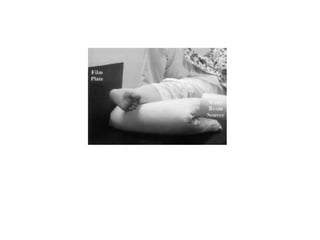

• Intra operative stress testing:

(1)Lateral force to heel to displace the fibula

laterally (cotton’s test)

(2)Pulling the fibula laterally with a hook (hook

test) – most popular by the surgeons

(3)External rotation stress test

cotton’s test

Hook test